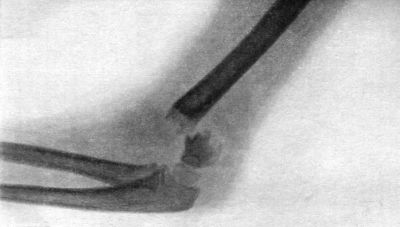

35.Radiogram of Fracture of Olecranon Process86

36.Backward Dislocation of Elbow in a Boy89

37.Bony Outgrowth in relation to insertion of Brachialis Muscle90

38.Radiogram of Incomplete Backward Dislocation of Elbow91

39.Forward Dislocation of Elbow, with Fracture of Olecranon93